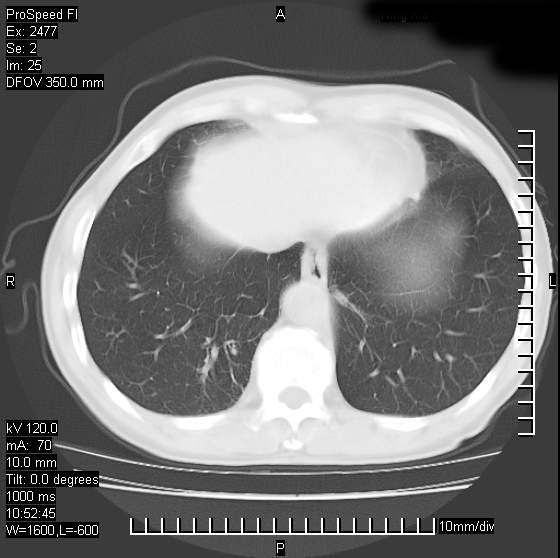

以下是引用天南地北在2007-10-9 14:29:00的发言:[br]1:右上肺结核[br]2:右肺下叶肿块:不支持肺癌,首先考虑炎性病变-肺脓疡可能性大[br]理由:1:临床病史支持,肺脓肿症状不明显应该是不规则服药造成。[br] 2:肿块边缘模糊,周围可见炎性渗出,长毛刺,内见支气管征,不过有点不规则。[br] 我感觉下肺癌这个诊断有点偏左,建议积极抗炎治疗后复查

以下是引用卜一在2007-10-9 15:55:00的发言:[br][br] [br] 1:右上肺结核[br]2:右肺下叶肿块:不支持肺癌,首先考虑炎性病变-肺脓疡可能性大[br]理由:1:临床病史支持,肺脓肿症状不明显应该是不规则服药造成。[br] 2:肿块边缘模糊,周围可见炎性渗出,长毛刺,内见空气支气管征,不过有点不规则。[br] 我感觉下肺癌这个诊断有点偏左,建议积极抗炎治疗后复查![br]支持! [br] [br] [br]

以下是引用wxy7406在2007-10-9 21:02:00的发言:[br]结合临床病史首先考虑感染性病变,但周围型肺癌不能除外,1.患者年龄偏大2.临床有咯血3.(也觉得是最重要的一点)病灶内有偏心性空洞。

以下是引用王仕学在2007-10-9 13:48:00的发言:[br]右下肺周围性肺癌可能性大,最好活检吧

以下是引用hhcckk在2007-10-9 15:18:00的发言:[br]右上肺病灶考虑结核,病灶多种形态并存(纤维化、增殖性病灶并存)[br]右下肺病灶比较难说,个人意见更趋向于“天南地北”的诊断----肺脓肿[br]1、病人有明显的寒战,高热,肿瘤病人很少出现[br]2、病灶周围的肺纹理走向柔和,没有肿瘤病灶常见的集束征[br]3、病灶边缘的毛刺较长,恶性肿瘤多为短毛刺[br]痰中血丝和病人的年龄是两个不利于良性肿块的因素,建议早点活检

以下是引用ydx_74在2007-10-9 15:53:00的发言:[br]右上肺结核,右下中心性肺癌可能大,肺门淋巴结肿大。